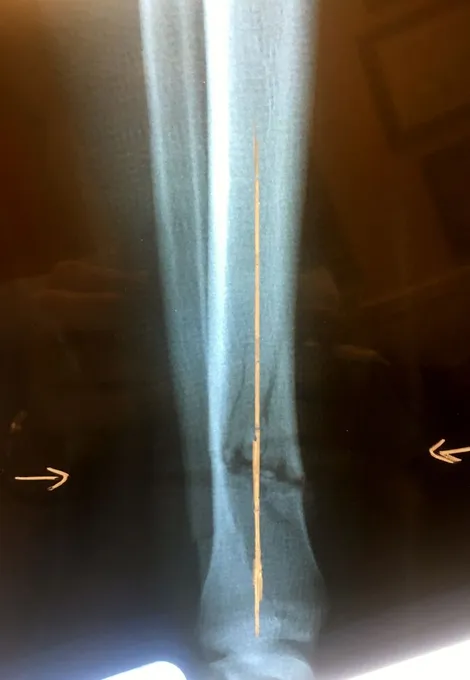

Pictures below show a 60 year old woman who fell getting out of bed and broke the shaft of her tibia as has a distal fibular fracture. This was treated with an Intramedullary rod as well as a surgical plate and fixation with screws of the fibular fracture.

Displaced Tib-fib fracture that was treated with IM rod of the Tibia (below)